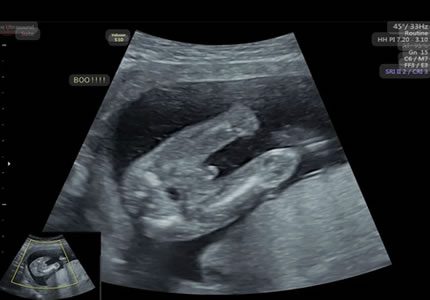

Growth & Late Pregnancy Scans (24 – 36+ Weeks)

- Preparation is key for a confident birth. We confirm your baby’s orientation (such as head-down or breech) and check the placenta site. This information is vital for finalising your birth plan with your midwife or consultant as your due date approaches.